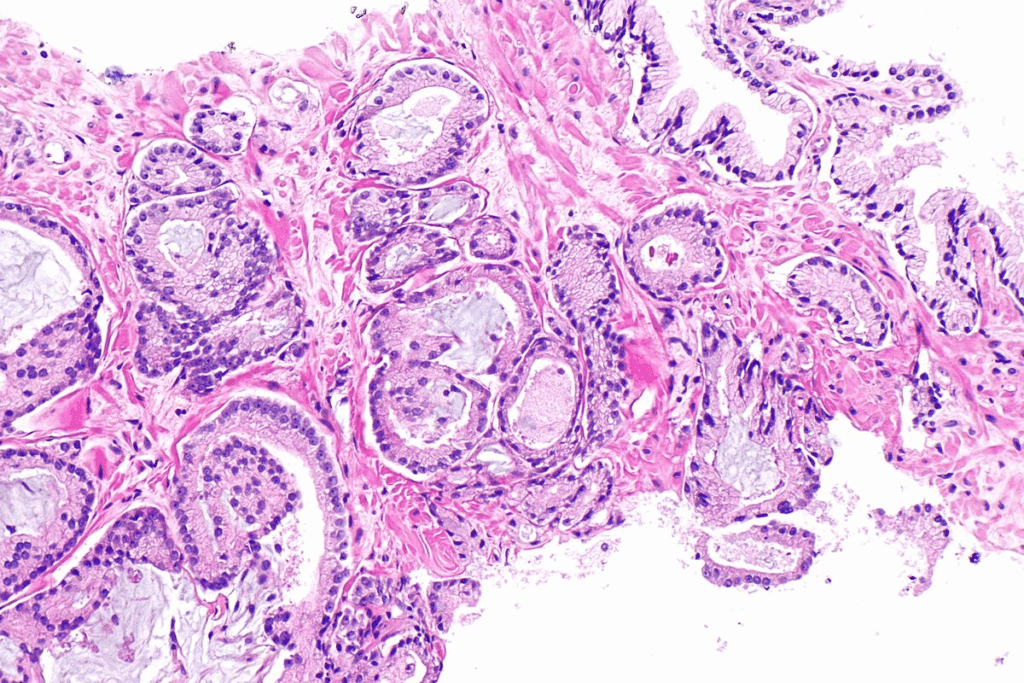

Cellular Characteristics and Pathology

CIS bladder cancer has high-grade malignant cells. These cells are in the urothelium but don’t invade the bladder wall. They have big nuclei and prominent nucleoli, showing they are high-grade.

Doctors look closely at these cells to diagnose CIS. They use cystoscopy, biopsy, and histology. These cells can become aggressive and lead to invasive cancer if not treated.

Absence of Papillary Formation

CIS doesn’t form papillary structures like some bladder cancers do. Its flat appearance is a key diagnostic feature. This makes CIS different from low-grade papillary urothelial carcinomas.

Because CIS is flat, it’s hard to spot with cystoscopy alone. A detailed diagnosis is needed to find CIS.

A biopsy is needed to confirm CIS. Doctors take samples from the bladder during cystoscopy. These are then checked under a microscope. Finding high-grade urothelial carcinoma without papillary formation means it’s CIS.